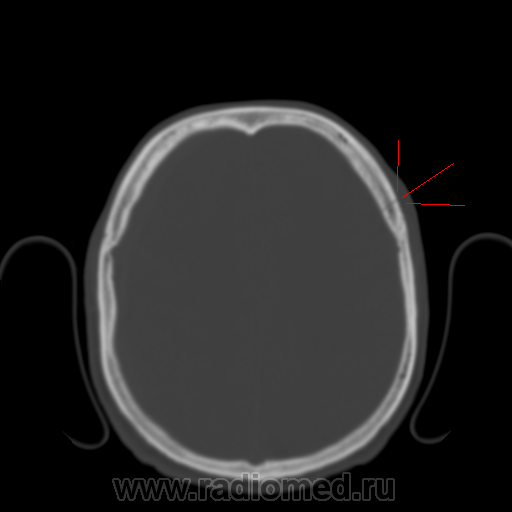

Молодой человек, поступил в экстренном порядке, в тяжелом состоянии, на МСКТ-головного мозга субдуральная гематома справа(конвексиально-гиперденсивная полоса, отмечена красной стрелкой), как видно имеется дислакационный синдром, правый боковой желудочек компремирован:

В костном режиме видно линейный перелом лобной кости слева: